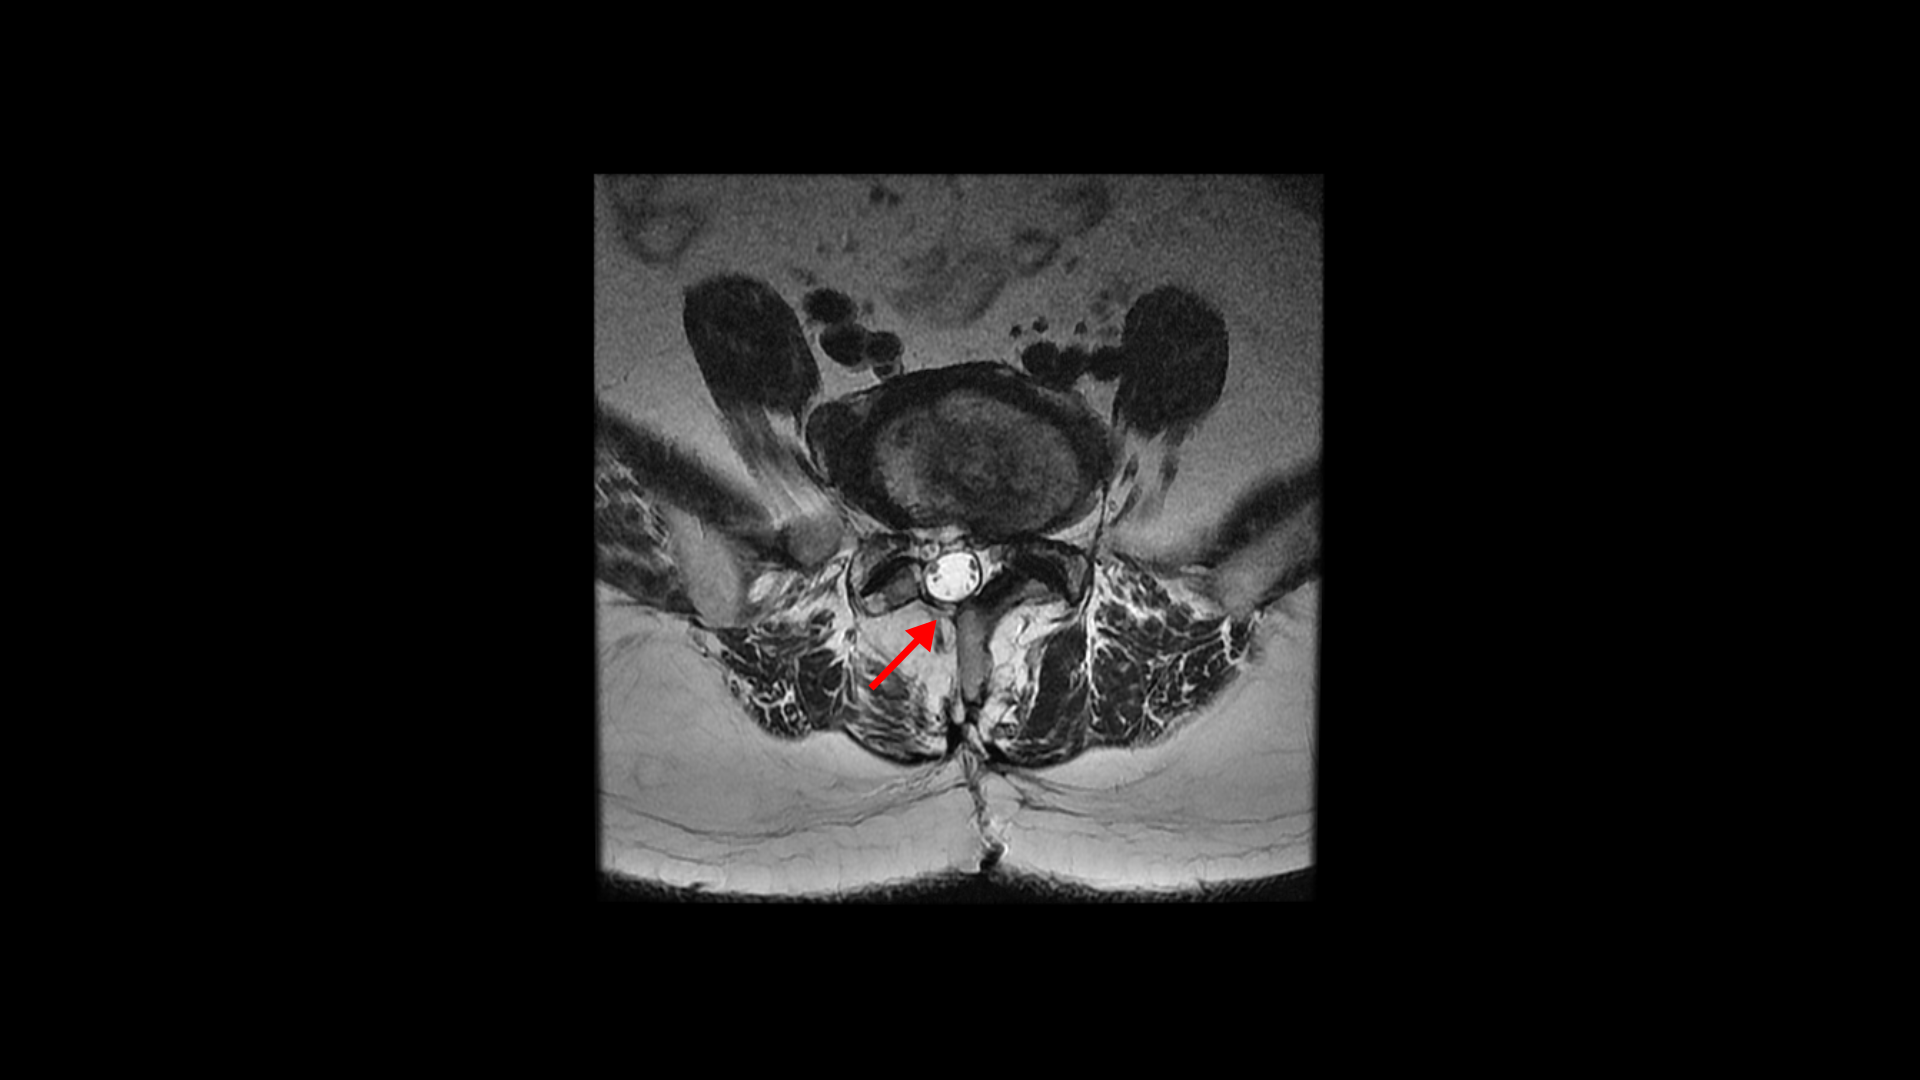

이 환자분은 허리수술을 여러 번 한 상태에서 결국에는 척추유합술까지 하셨습니다. MRI를 보시면 5번 1번 후궁에 수술한 자국이 보입니다.

4번 5번 후궁 양쪽으로 수술한 자국이 보입니다.

올해 초에 4번 5번 디스크가 또 오른쪽으로 심하게 파열돼서 결국 후궁과 후관절, 황색인대를 모두 다 제거하고 나사를 박는 척추유합술을 하셨습니다.

그런데 척추유합술을 하고 난 후 오른쪽 다리의 증상은 호전되었으나 상대적으로 증상이 괜찮았던 왼쪽 다리에 심한 방사통과 마비 증상을 호소하셨습니다. 수술한 병원의 집도의로부터 수술은 잘 됐으나 수술한 자리가 부어있기 때문에 신경을 눌러서 그런 거라고 1년 이상 기다리면 회복될 것이라는 얘기를 들으셨다고 합니다.